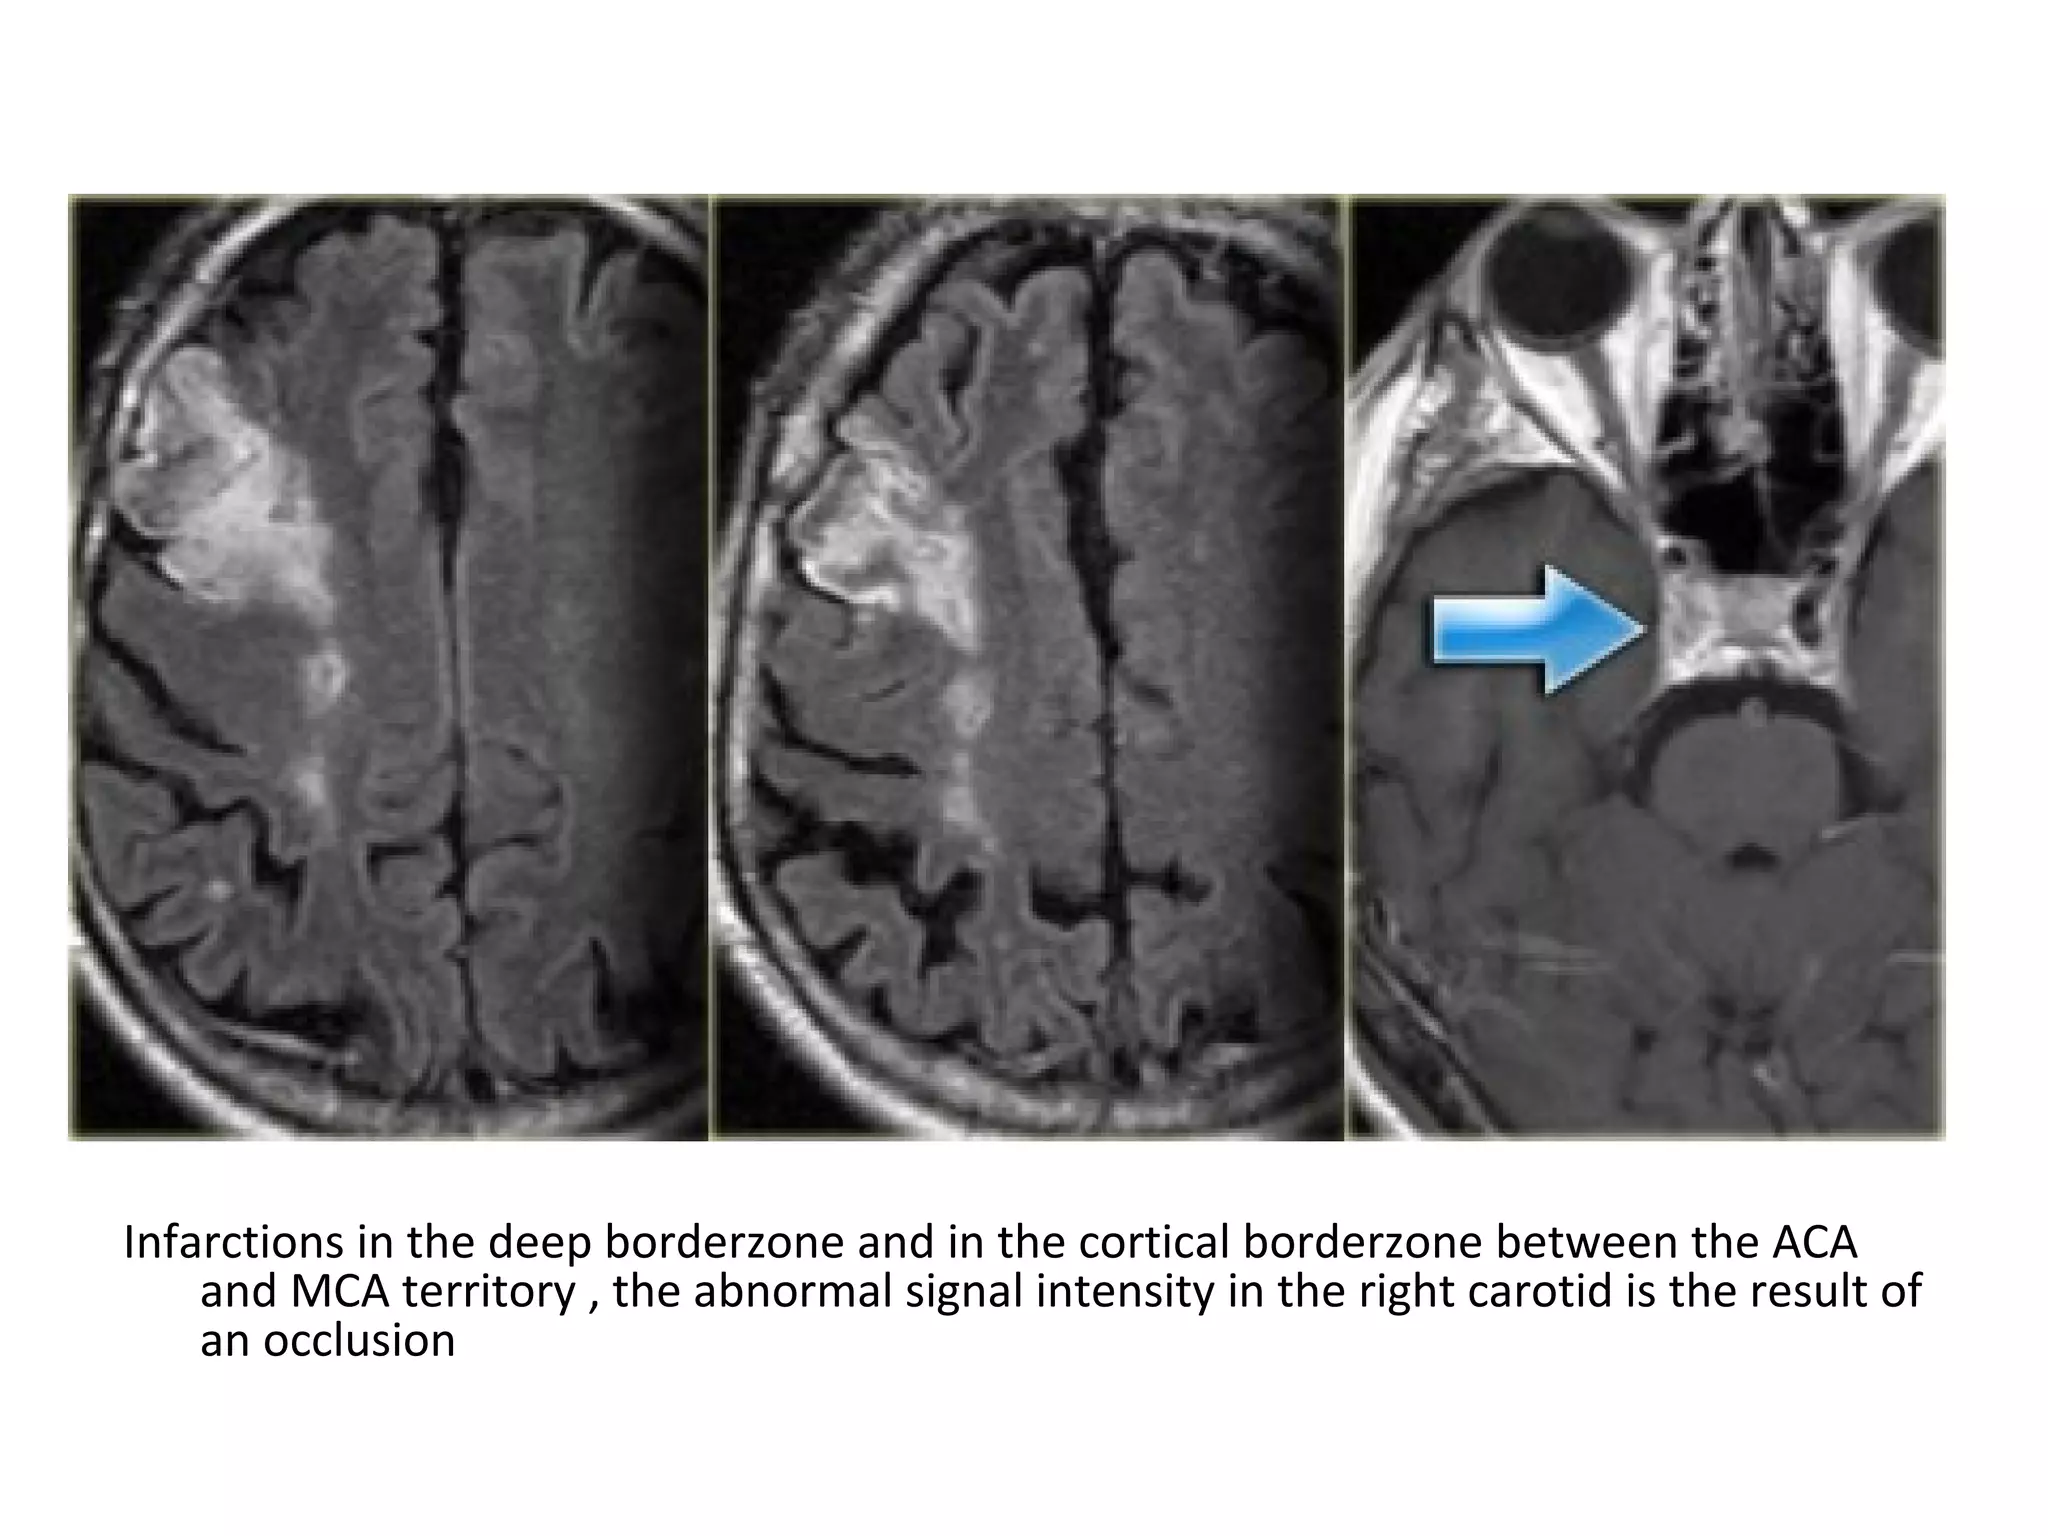

A patient with an occlusion of the right internal carotid artery , the hypoperfusion in

the right hemisphere resulted in multiple internal border zone infarctions, this

pattern of deep watershed infarction is quite common and should urge you to

examine the carotids

Small infarctions in the right hemisphere in the deep border zone (blue arrowheads)

and also in the cortical border zone between the MCA & PCA territory (yellow

arrows) , there is abnormal signal in the right carotid (red arrow) as a result of

occlusion

Small infarctions in the deep border zone and in the cortical border zone

between the MCA & PCA territory in the left hemisphere

Infarctions in the deep borderzone and in the cortical borderzone between the ACA

and MCA territory , the abnormal signal intensity in the right carotid is the result of

an occlusion